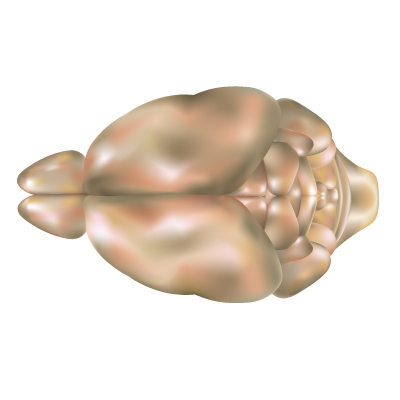

У једном од најимпресивнијих подухвата у неуронауци, тим истраживача је, користећи суперрачунар Fugaku, створио виртуелну верзију мождане коре миша која је невероватно детаљна. Ова дигитална симулација, за коју многи кажу да је најживља до сада, омогућава научницима да прате неуронску активност у виртуелном мозгу и живи орган. Како је направљен виртуелни мозак?

Основу чине огромне биолошке базе података које је обезбедио Институт Ален. Реч је о јасној мапи типова неурона, њихових међусобних веза и структуре. Затим је све то оживљено захваљујући суперрачунару, који је један од најмоћнијих на свету и способан је да израчуна квадрилионе операција у секунди. У моделу је симулирано близу десет милиона неурона, који су повезани са око 26 милијарди синапси, а сам виртуелни мозак обухвата 86 међусобно повезаних подручја мождане коре. Оно што је заиста импресивно јесте да се прати и кретање јона кроз мембране неурона, варијације електричног набоја унутар различитих делова једног неурона и активност синапси.

Истраживачи користе алате као што су Brain Modeling ToolKit и Neulite дa математичке једначине претворe у виртуелне неуроне који комуницирају једни с другима, баш као прави. Зашто је овај модел велики корак напред? До сада су експерименти на живом ткиву или животињама били дужи, сложенији и ограничени. Са овим виртуелним мозгом научници могу посматрати како праве болести, попут Aлцхајмерове или епилепсије, настају и развијају се корак по корак у дигиталном окружењу.

Међутим, истраживачи и сами признају да ово није крај. Модел је заснован на мишијем мозгу јер, иако миш представља важан модел организма за људски мозак, он није његова директна копија. Ипак, ово је огроман корак ка амбицији да се једног дана направи симулација целог мозга – можда и људског, са биофизичким детаљима. Aркхипов и тим истраживача виде будућност у којој је такав модел реалност, а не научна фантастика.

(Илустрација Wikimedia Commons)